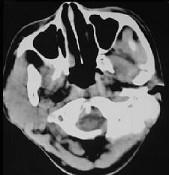

问题 女性,19岁,右侧面颊部肿胀1年,CT检查如图所示,请选择最佳答案()

选项 A.右颊部神经纤维瘤 B.右颊部血管瘤 C.右颊部脂肪瘤 D.右颊部横纹肌肉瘤 E.右颊部血肿

答案 B